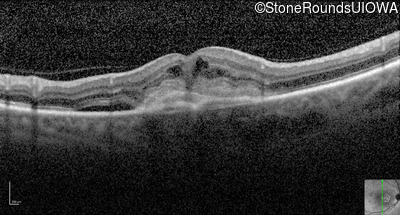

Optical Coherence Tomography - Right - 20/80 +1

Exemplar / OCT Stack